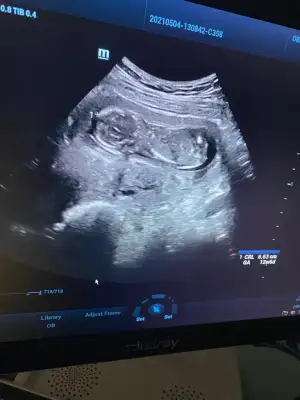

İnşallah dediğiniz gibi olur kızlar ama hiç zannetmiyorum benim 2 kızımada devlette 12 haftada kız dediler değişmedi, bugün özeldeydik renkli renksiz bütün usg lere baktı yarım saat inceledi neredeyse, pozisyonuda uygundu bacak arası boştu ben biile gördüm, ben değişceğini düşünmüyorum kız olduğunu kabullendim hayırlısı böleymiş 😍😍😍

• IMG-20210504-WA0019.webp

IMG-20210504-WA0019.webp

33,9 KB · Görüntüleme: 70

Ya doktor zaten dediki ben normLde 14 haftdan önce kesinbelli olmadan cinsiyet söylemiyorum, ama ben başından beri aynı doktora gidiyorumya biliyor mevzuları erkek istediğimi upraştıpımı filan bugün o benden meraklıydı yani düşün, o yüzden çok inceledi yani o yine kesin değil amabacak arası boş dedi sadece3 hafta sora gel netkeşir kesin kız diyemem dedi, amaarkadaşım 11 +3 tü cuma günü erkek dedi ona doktor yani ben bugün 12+6 bu kadarda gelişmiş ultrasyonda bide öle yakınlaştırdıki o demeden ben gördüm hemen dedim oğlan olaydı en azından bi ufak çıkıntı olurdu diye, çünkü bacak arasını net gördük, benim için mucize öyle birşey olmayacak değişmiyecekte yinede inş diyeyim 🤲🤲